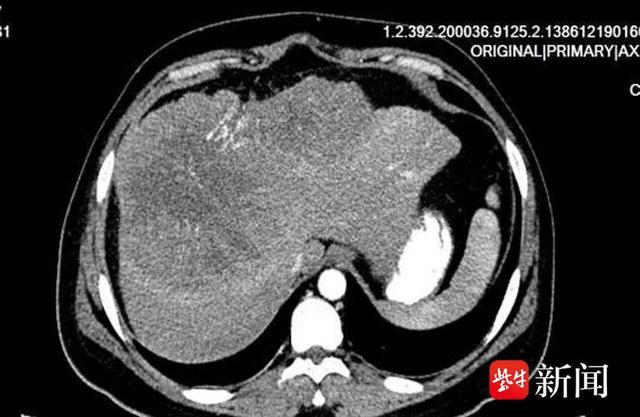

影像检查显示张先生肝脏存在直径约22cm巨大肿瘤 住院后,考虑到张先生体内肿瘤巨大,随时有破裂风险,充分考虑各种因素后,祁付珍主任组织多学科团队反复讨论推演,制定了符合患者的最佳手术方案和预案,明确了手术方式和术中、术后应急预案,保障患者得到规范、个体化的诊疗。